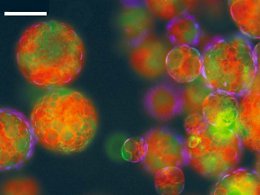

Новая вакцина, основанная на наночастицах, защитит от сибирской язвы и чумы

Исследовательская группа в Соединенных Штатах разработала двойную вакцину на основе наночастиц против Bacillus anthracis и

Исследовательская группа в Соединенных Штатах разработала двойную вакцину на основе наночастиц против Bacillus anthracis и